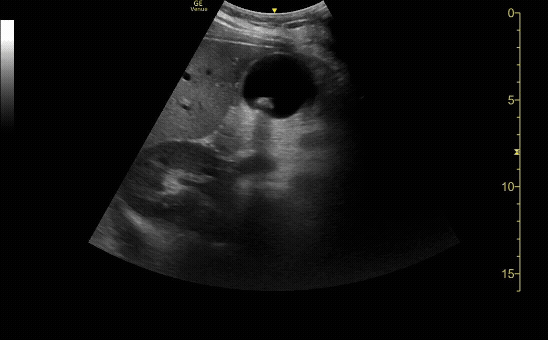

Common bile duct (if visualized) measuring <0.6cm with color flow seen in the portal vein.

c/o Jose Reyes, MD